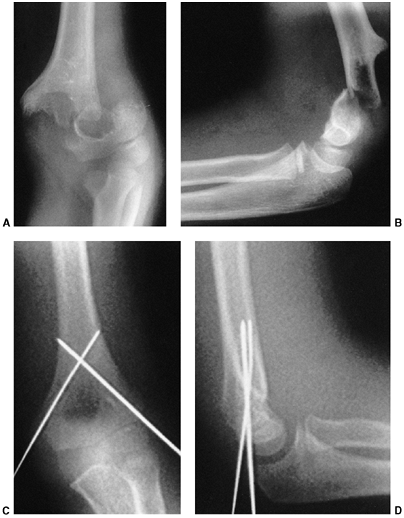

displaced. Treatment begins with a complete assessment of perfusion and

nerve function. Neurovascular problems are frequent, and fracture